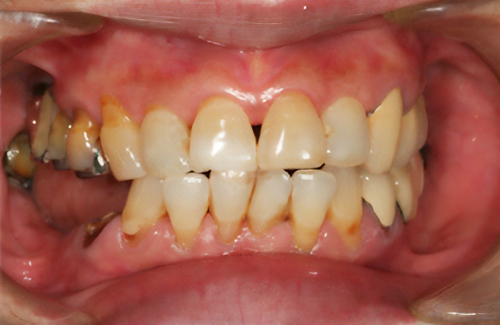

歯の形、歯並び、歯肉ラインが整う美しい口元

大掛かりな歯ぐきの手術や装置を使った矯正治療を行わずに、たった2回で歯並びをきれいに整えることができます。

術前

-

術後

BTAテクニック® とは

従来のセラミックで治すオールセラミックという被せ物や、セラミックを張り付けるラミネートべニアという方法に、歯科医師と歯科技工士の双方の手法と技法を癒合させることで、可能とした 歯ぐきのラインを2回の来院で、綺麗に仕上げ、歯の見た目も審美的に出来るテクニックのことである。

BTAテクニック® 以外の一般的な治療で歯ぐきのラインを整えるには、歯ぐきを切り、骨を削る手術をすれば可能ですが、歯ぐきの治りに数か月の期間が必要です。もしくは、矯正治療によって、歯並びを改善する方法、もしくは神経を抜いて、被せ物をするしかありません。

BTAテクニック® を用いると、歯ぐきや骨への手術が必要ない為に、治療期間が短縮でき、2回の来院で完了できるメリットがある。 また、この方法を用いることで、年々歯ぐきが下がって見た目が悪くなるということが起きにくくなる。歯周ポケットと言われる溝が浅くなり、歯ブラシが容易になる。などの利点が挙げられる特殊なテクニックである。

また、救歯BTAセラミックは、BTAテクニック®が持つ成功する理由(*)から、深い位置まで虫歯が進行してしまって歯を抜かないとならない歯に応用する事で、抜かずに治療することが出来る場合がある。

症例によっては、BTAテクニック® , 救歯セラミックが適応出来ない場合があります。 また、この方法を用いることで必ず歯が残せるという治療方法ではありません。

価格

> 1歯 165,000円